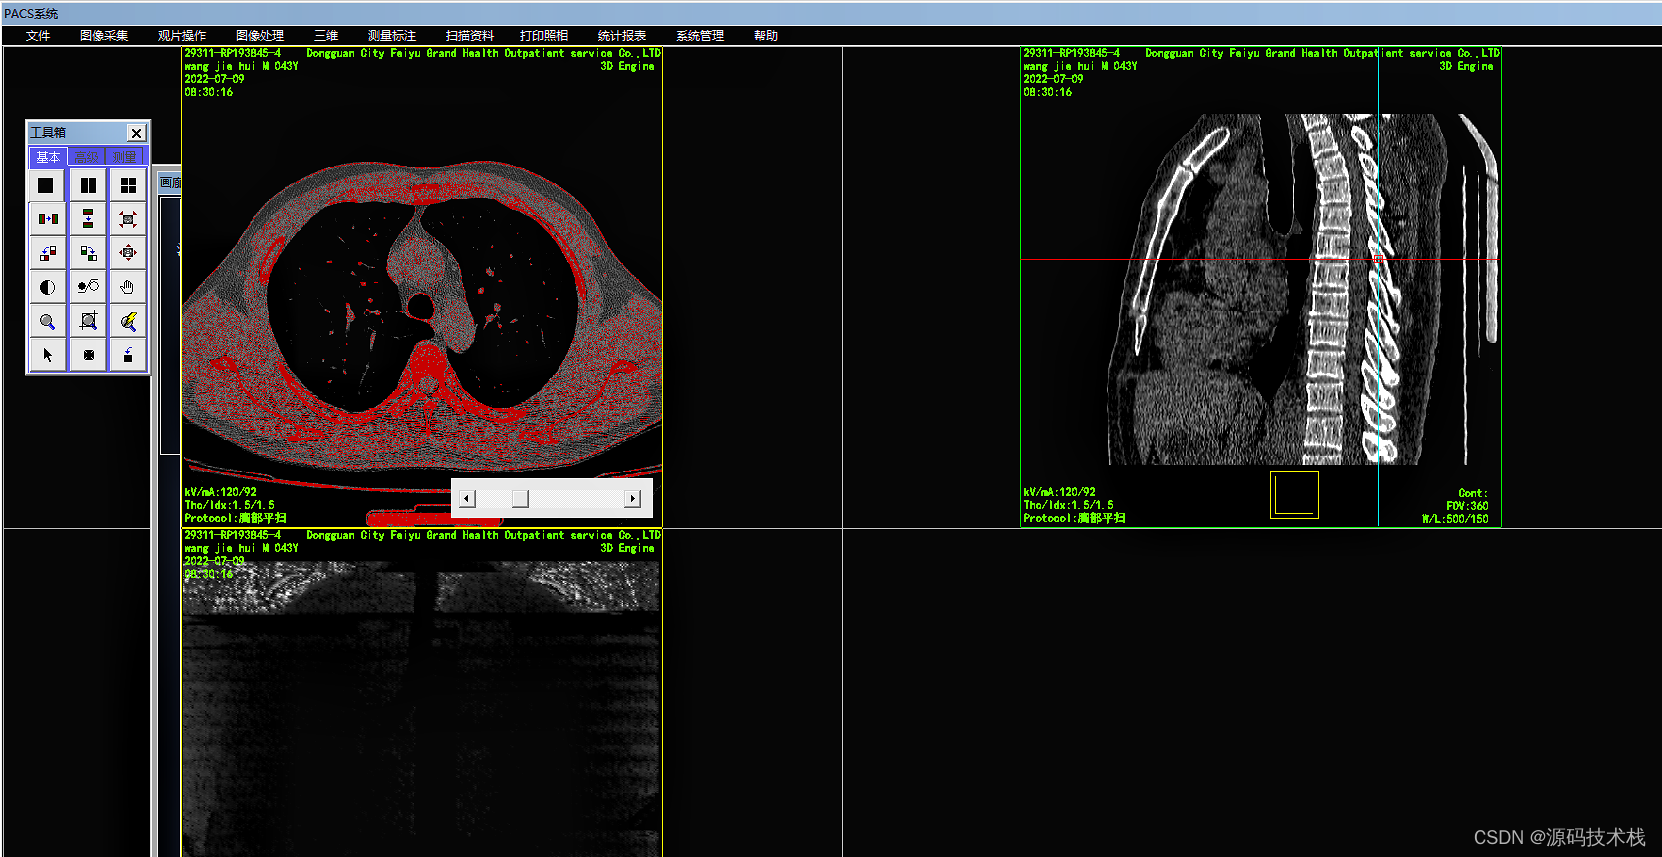

影像查阅

系统采用DICOM和非DICOM格式获取影像数据,以通讯方式采集影像原始DICOM数据;

支持静态和动态影像数据采集;

支持透视采集和曝光采集等多种采集方式;

支持非DICOM影像设备的影像数据转化为DICOM标准的数据。

支持读取DCMDIR文件,显示并打开相关联的DICOM文件;

显示多种图像文件格式,并能转换成DICOM格式;

支持多屏和竖屏显示;支持动态影像电影方式回放、逐帧漫游和冻结;

支持同屏显示多幅影像,自定义显示矩阵;

支持同屏显示同一患者在不同检查设备检查的多个动态电影图像;

支持检查模式、比较模式和打印模式的图像显示;

支持多屏显示同一患者的不同序列图像或不同患者的图像;

支持同屏分格显示患者不同体位和不同设备的影像;

支持不同患者间的影像对比。

图像后处理与重建

·MPR\CPR(三维多平面重建)

·VRT(三维容积重建)

·SSD(三维表面重建)

·VE(虚拟内窥镜)

·MIP(最大密度投影)

·MinIP(最小密度投影)

·CalSCore(心脏图像冠脉钙化积分)

影像处理和测量功能

系统支持支持窗宽、窗位预设,连续调整窗口准位和直方图,图像均衡、图像平滑处理和边缘增强;

支持对比度调节、正负像旋转、影像黑白反转、影像水平和垂直翻转、灰阶转换和任意角度旋转等;

支持滤波、锐化、播放和彩色绘制等;

支持ROI值、长度、角度和面积等数据测量与计算;

支持数字减影、无级缩放和局部放大;

支持文字和图形标记;查询和保存DICOM头信息;

支持不同影像格式转存;

支持根据检查项目自动应用相应的预设窗宽、窗位。